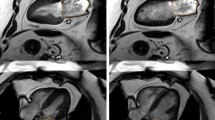

Cine images were analyzed using semi-automated cvi42 software (Circle Cardiovascular Imaging, Calgary, Canada) by a single experienced observer (PK), blinded to all clinical data. All volumetric and mass data were indexed to body surface area (BSA). Ventricular volumes (see Fig. 1), ejection fraction and LV mass (excluding papillary muscles) were calculated from the short-axis cine stack as previously described [10, 15]. The biplane method, excluding the appendage and pulmonary veins was used to measure maximal, minimal left atrial volumes (LAVmax, LAVmin) and derive left atrial ejection fraction (LAEF) [11]. A cut-off RVEF value of < 47% was used to define RVD based upon existing normative data from the published literature utilizing the same technique as in our study [16] as well as from our own healthy control data whereby the lower limit of RVEF was also 47%. Qualitative LGE assessment was undertaken by 2 experienced operators to define the presence of MI as per standard criteria [15, 17]. In cases of disagreement, final adjudication was deferred to a third operator (GPM). As previously reported by our group with excellent reproducibility [18] and intra/inter-observer agreements [15], extracellular volume (ECV) and indexed ECV were quantified from mid short-axis LV slice T1 maps.

Assessment of ventricular volumes, function and mass. End-diastolic (a) and end-systolic (b) cine frames illustrating manually drawn contours of the left ventricular endocardium (pink), left ventricular epicardium (green) and right ventricular endocardium (yellow) for volumetric and mass analysis. (white arrows) papillary muscles and trabeculations were excluded from left ventricular mass calculations